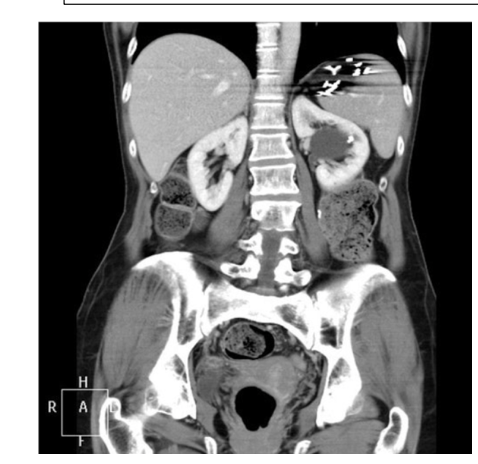

What is the CT + Pathology?

Abdomen CT C+

- In arterial phase as the abdominal

aorta has maximum opacification • Path = renal cell carcinoma

- Heterogenous mass on the kidney

with poorly defined margins